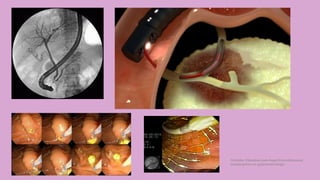

CPRE

(COLANGIOPANCREATOGRAFÍA

RETRÓGRADA ENDOSCÓPICA)

DEFINICIÓN

Intervención mixta

endoscópica (endoscopía

esofagogastroduodenal) y

radiológica, utilizada

para estudiar y,

principalmente tratar, las

enfermedades de los

conductos biliares y del

páncreas.

Técnica más

compleja de

la endoscopia

digestiva

Morbilidad

hasta 10%

Mortalidad

de 1%

INDICACIONES DE LA CPRE

Fístula biliar o fístula pancreática

Tumores

Cálculos biliares

Inflamación debido a traumatismo o enfermedad

Infección

Oclusión inadecuada de válvulas o esfínteres

Esclerosis de los conductos

INTERVENCIONES QUE SE PUEDEN

REALIZAN CON LA CPRE

Esfinterotomía o papilotomía (biliar o

pancreática)

Esfinteroplastía

Extraccion de litos del colédoco

Colocación de prótesis o stents para

estenosis (temporales o permanentes)

Córdoba Villalobos José Angel.Procedimientos endoscopicos en gastroenterología

EQUIPO ENDOSCÓPICO

• Aparato de visión lateral

• Ángulo de visión de 100%

• 11-13 mm de diámetro

• Conducto de operaciones 2,8-4,2 mm, >para

prótesis

• Elevador de catéter

y aditamentos

CATÉTER PARA CPRE

Tubo de teflón con 200 cm de long. X 1,7 mm

de diámetro (5 French)

Extremo proximal: estructura de plástico para

jeringa y entrada para mandril metálico de 100

cm

Extremo distal: punta de diferentes formas

según la función deseada

En los 15 mm distales del catéter hay 3 marcas

negras (profundidad de la canulación)